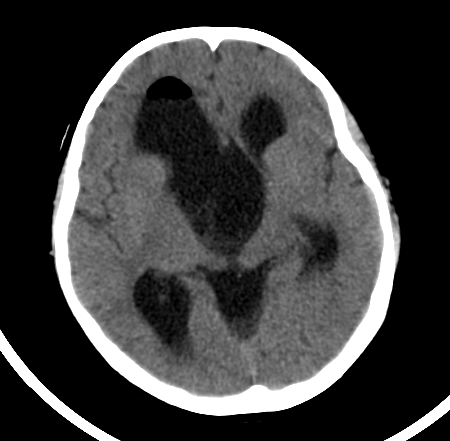

2岁的浩浩(化名)是个可爱男宝宝。一个月前家人发现他间断恶心、呕吐,在当地医院查了个头部的CT,结果显示浩浩左侧接近一半的脑子被一个巨大“水球”所占据,医学上叫做“中颅窝蛛网膜囊肿”。由于孩子太小,家人很是谨慎,经过多方打听了解到郑州大学五附院有神经内镜治疗颅内蛛网膜囊肿技术,于是转入神经外科三病区就诊。浩浩的病情得到了付旭东主任和麻醉科胡强夫主任及其团队的高度重视,为其制定了周密的手术方案,同样要把“死水”变成“活水”。在兄弟科室的通力合作下手术过程顺利,术后浩浩的症状明显改善,家人悬着的一颗心也终于落了地。同样由于神经内镜创伤小的优点,浩浩很快顺利康复出院。

左中颅窝巨大蛛网膜囊肿,占据了近一半脑子